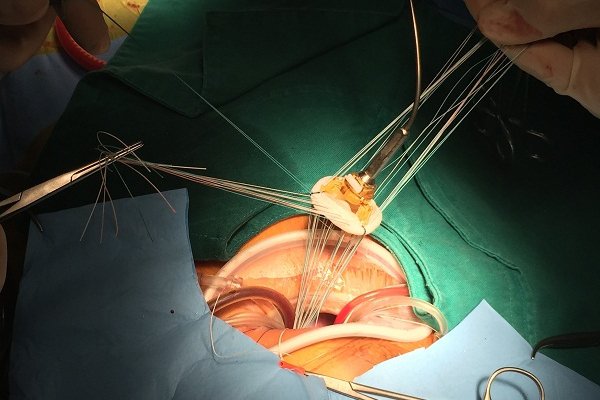

5.1. Trong quá trình thay van

Bệnh nhân sẽ nhận được thuốc gây mê để đưa họ vào trạng thái ngủ trong suốt quá trình phẫu thuật. Người bệnh sẽ được kết nối với một máy bắc cầu tim-phổi để giữ cho máu di chuyển khắp cơ thể trong suốt quá trình phẫu thuật.

Phẫu thuật van tim có thể được thực hiện bằng phương pháp phẫu thuật tim hở tiêu chuẩn, bao gồm cắt ngực qua xương ức. Phẫu thuật tim xâm lấn tối thiểu bao gồm các vết rạch nhỏ hơn so với các vết mổ được sử dụng trong phẫu thuật tim hở.

Phẫu thuật tim xâm lấn tối thiểu bao gồm phẫu thuật được thực hiện bằng cách sử dụng các dụng cụ dài chèn qua một hoặc nhiều vết rạch nhỏ ở ngực (phẫu thuật nội soi lồng ngực), phẫu thuật được thực hiện qua một vết rạch nhỏ ở ngực hoặc phẫu thuật do bác sĩ phẫu thuật thực hiện với sự hỗ trợ của rô bốt (rô bốt- hỗ trợ phẫu thuật tim).

5.3. Thay van tim

Nếu van tim không thể được sửa chữa và thủ thuật dựa trên ống thông không phải là một lựa chọn, thì van có thể cần được thay thế. Để thay van tim, bác sĩ sẽ loại bỏ van tim và thay thế bằng van cơ học hoặc van làm từ mô tim của bò, lợn hoặc người (van mô sinh học).